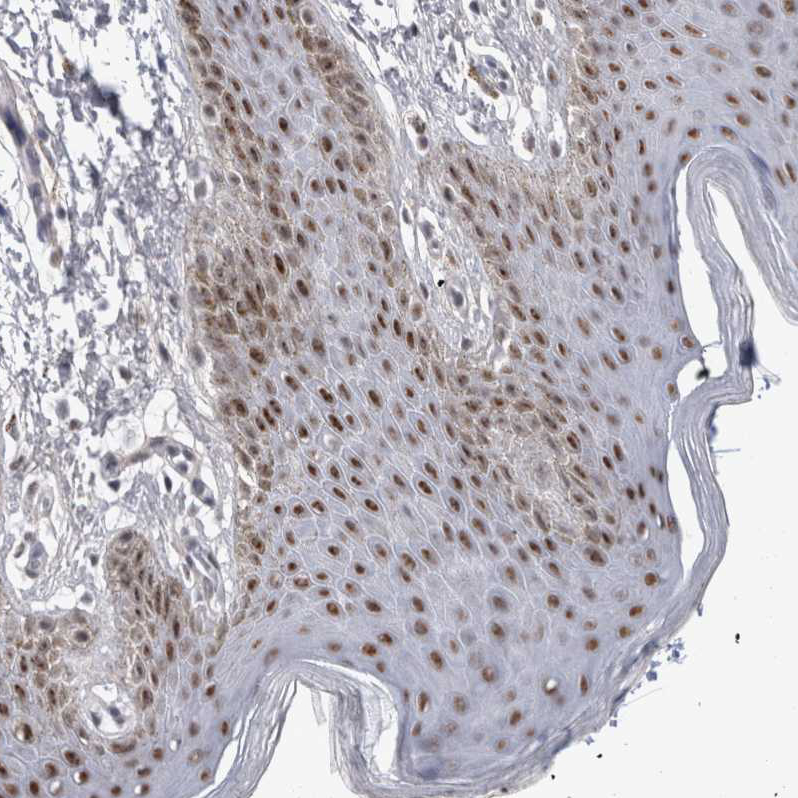

Immunohistochemical staining of human urinary bladder shows strong nuclear positivity in urothelial cells.